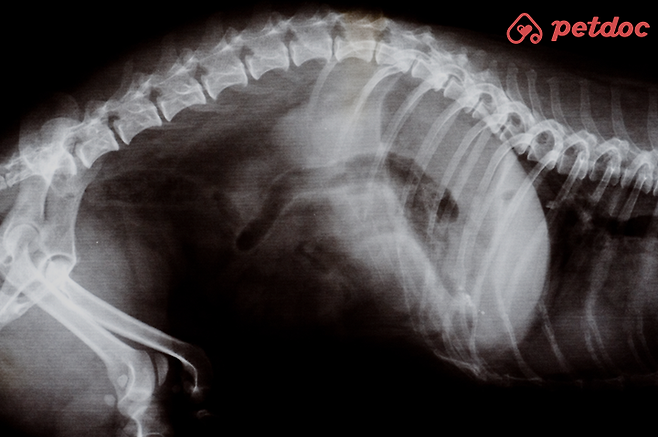

특히 그 중에서도 '디스크 질환'은 초기에 발견할수록 약물이나 침 치료만으로도 결과가 좋아져요. 하지만 늦게 발견할 경우 심한 마비가 올 수 있어요.

건드리지도 않았는데 갑자기 깨갱거리며 비명을 지르는 경우를 보셨나요? 보통은 두 가지로 볼 수 있는데요. 척추, 디스크, 관절 쪽의 통증이 있을 때 몸이 아프다는 신호를 이런 방식으로 강하게 보내요. 두 번째로는 학대나 반복적인 폭행을 당한 기억이 있을 경우 아픈 곳이 없어도 이런 행동을 보이는 경우가 있어요.